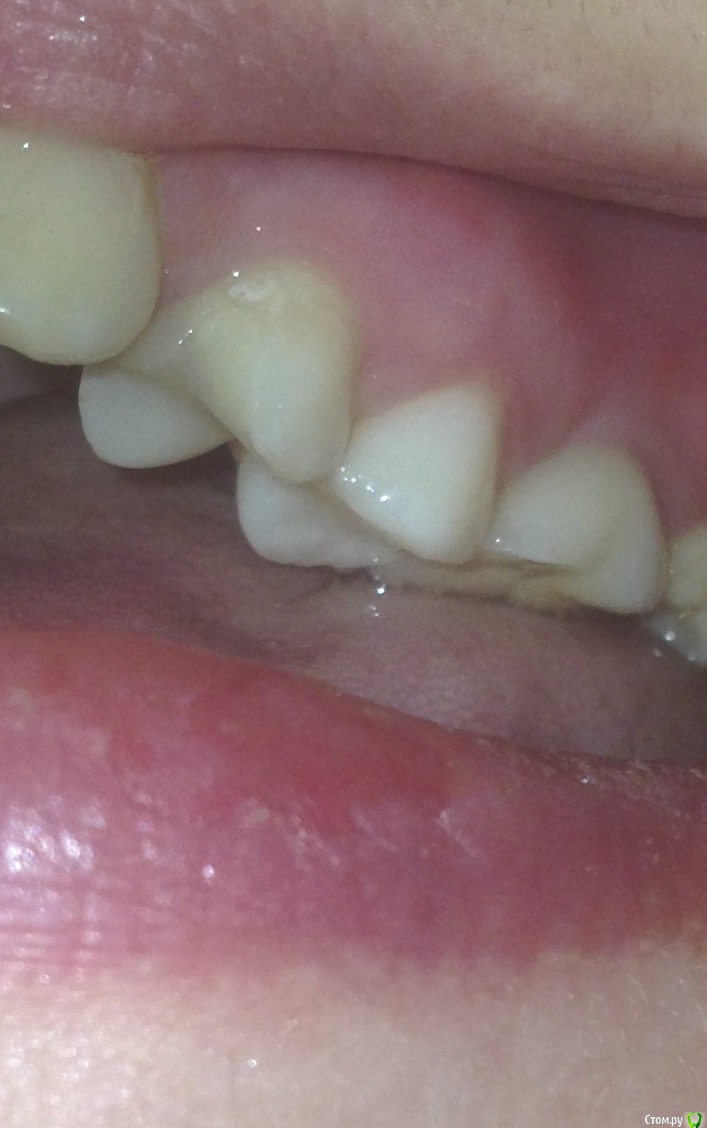

Карман в области 25 и свищ

Никто не знает что с этим делать, сказали что пища попадает из за этого подтекает, Ещё 8 на имплант давит и может его расшатать правда такое возможно? Сказали купить ирригатор и постоянно мазать метрогилом. Нерв удалён почти 10 лет назад, пролечен зуб качественно, карман и свищ образовались в этом году.

Вот старый снимок, лучше видно как залечен зуб и свежее фото, сохраняется отёк, болит если надавливать.